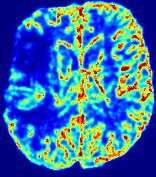

4.3.1 Advection Imaging via Advection-Diffusion

Slice #1Slice #2Slice #3Slice #4Slice #5Slice #6𝐕gt𝟐subscriptnormsuperscript𝐕gt2\|\bf{V}^{\text{gt}}\|_{2}Refer to captionRefer to captionRefer to captionRefer to captionRefer to captionRefer to caption𝐕est𝟐subscriptnormsuperscript𝐕est2\|\bf{V}^{\text{est}}\|_{2}Refer to captionRefer to captionRefer to captionRefer to captionRefer to captionRefer to captionRefer to caption1.51.51.51.21.21.20.90.90.90.60.60.60.30.30.30.00.00.0(mm/s)𝑚𝑚𝑠(mm/s)Destsuperscript𝐷estD^{\text{est}}Refer to captionRefer to captionRefer to captionRefer to captionRefer to captionRefer to captionRefer to caption0.0150.0150.0150.0120.0120.0120.0090.0090.0090.0060.0060.0060.0030.0030.0030.0000.0000.000(mm2/s)𝑚superscript𝑚2𝑠(mm^{2}/s)

Figure 14: PIANO identifiability testing: advection imaging via advection-diffusion. Top row shows 𝐕gt2subscriptnormsuperscript𝐕gt2\|{\bf{V}}^{\text{gt}}\|_{2} used for simulating ground truth pure advection. Rows below show the estimated 𝐕est2subscriptnormsuperscript𝐕est2\|{\bf{V}}^{\text{est}}\|_{2} and Destsuperscript𝐷estD^{\text{est}} on corresponding slices. Note that the plotted value scale for Destsuperscript𝐷estD^{\text{est}} is 0.01 of that for 𝐕gt2subscriptnormsuperscript𝐕gt2\|{\bf{V}}^{\text{gt}}\|_{2} and 𝐕est2subscriptnormsuperscript𝐕est2\|{\bf{V}}^{\text{est}}\|_{2}.

We use the same ‘Advection Imaging’ simulation of Sec. 4.2.1 as the concentration dataset for PIANO. However, instead of modeling pure advection (Eq. 15), we let PIANO estimate both velocity 𝐕estsuperscript𝐕est{\bf{V}}^{\text{est}} and diffusivity Destsuperscript𝐷estD^{\text{est}} via the advection-diffusion PDE (Eq. 2) underlying the proposed PIANO model. Fig. 14 shows the estimated 𝐕est2,subscriptnormsuperscript𝐕est2\|{\bf{V}}^{\text{est}}\|_{2}, and Destsuperscript𝐷estD^{\text{est}} fields for one patient. Although PIANO has the freedom to estimate both a velocity and a diffusivity field from pure advection, PIANO differentiates well between advection and diffusion: the estimated 𝐕est2subscriptnormsuperscript𝐕est2\|{\bf{V}}^{\text{est}}\|_{2} successfully reproduces the ground truth 𝐕gt2subscriptnormsuperscript𝐕gt2\|{\bf{V}}^{\text{gt}}\|_{2} governing the simulated advection process, just as it already did in the ‘Advection Imaging via Advection’ test (Fig. 12). More importantly, the estimated diffusivity Destsuperscript𝐷estD^{\text{est}} is orders of magnitudes smaller than 𝐕est2subscriptnormsuperscript𝐕est2\|{\bf{V}}^{\text{est}}\|_{2}, indicating the estimated diffusion is negligible compared to the estimated advection, which is highly consistent with the underlying pure advection of the simulated data.